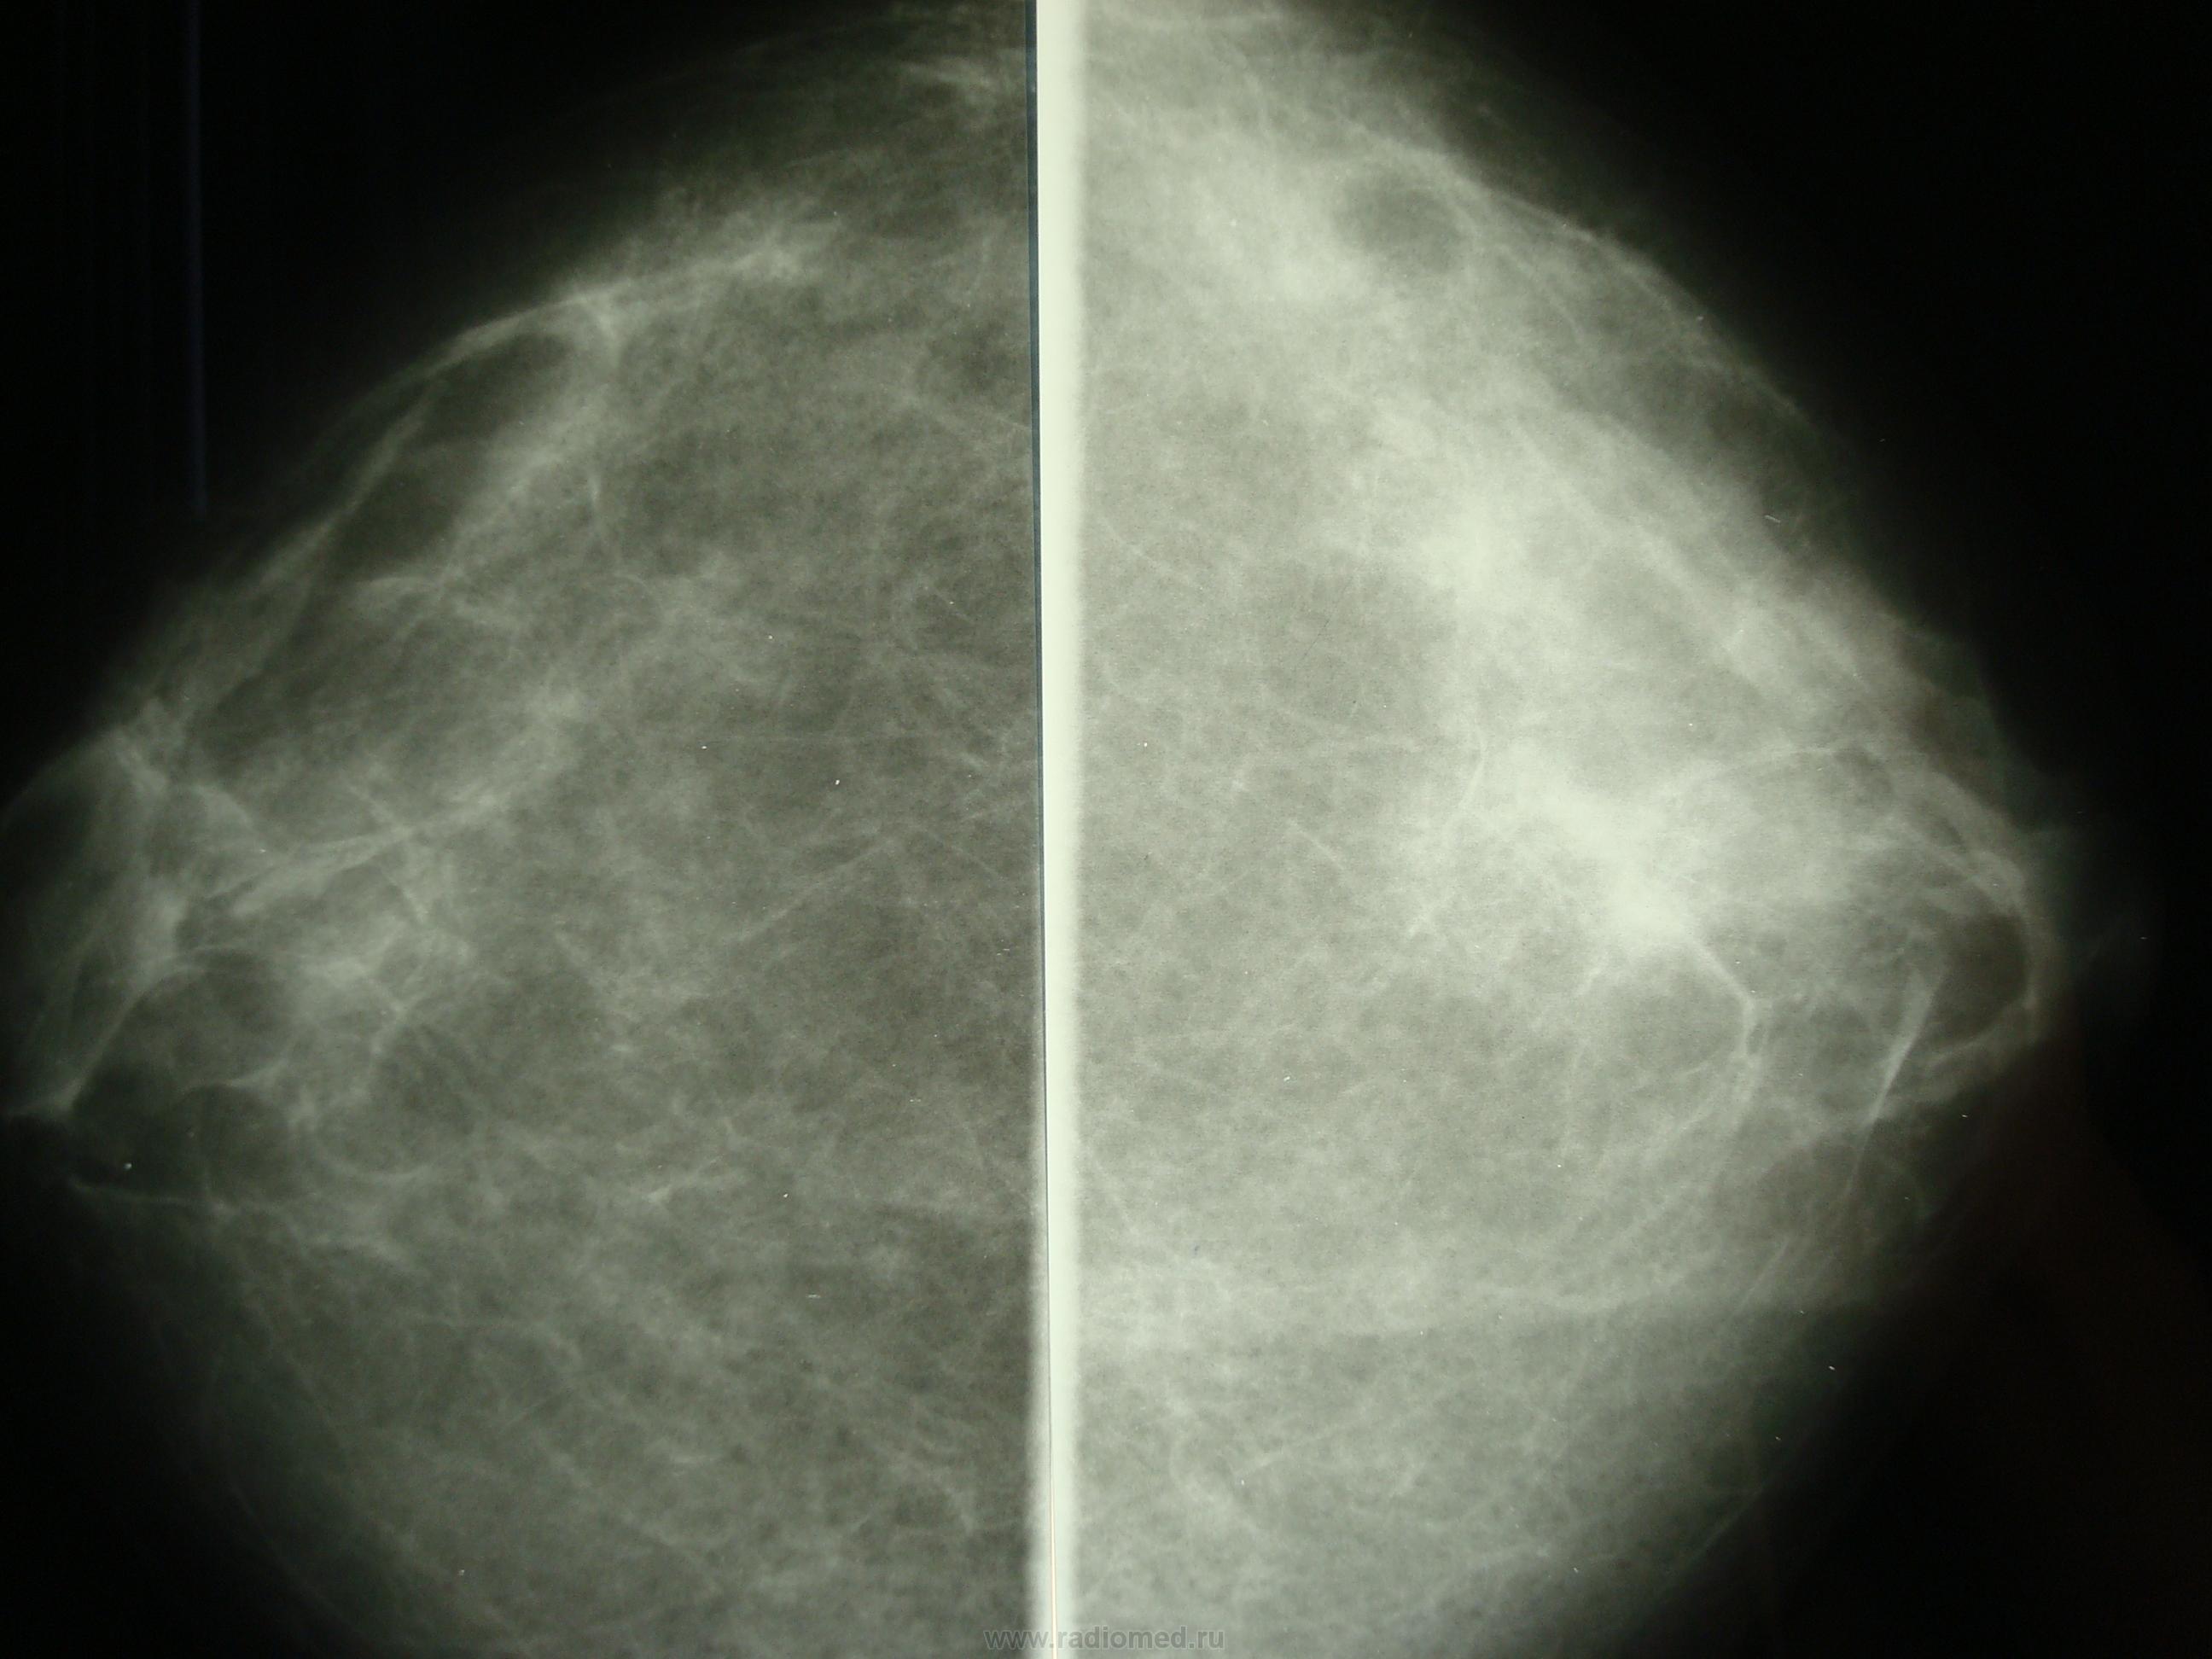

Фиброаденома молочной железы - доброкачественное образование, которое часто встречается у женщин. Оно может быть обнаружено при помощи различных методов диагностики, включая маммографию. Ниже представлены фотографии, помогающие понять, как выглядит данное заболевание.

Маммография и ее роль в диагностике фиброаденомы молочной железы

Маммография - это рентгенологическое исследование молочных желез. Оно позволяет выявить различные изменения в тканях, включая фиброаденому. На маммограммах можно увидеть структурные особенности опухоли и отследить ее динамику во времени.